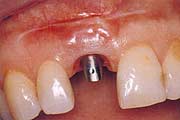

Wann machen Implantate Sinn?

Einzelzahnersatz

Gesunde Nachbarzähne müssen nicht beschliffen werden. Eine

unauffällige und natürliche Lösung. Anspruchsvoll in

der Ästhetik und langfristig im Nutzen.